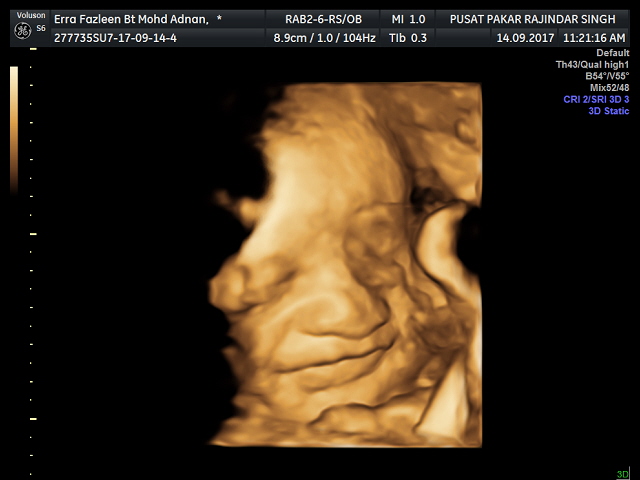

After a few times my husband ask me to go to scan. I don't know why, maybe he is excited to meet his little junior soon. Lagipun dah lama tak scan. Sebelum ni dia pernah ikut pergi scan sekali, then baru dia tahu perasaan seronok + teruja tengok anak sendiri dalam perut kot.! HAHA

So i went to scan this morning. Today my baby is officially 34weeks and 2 days. Kalau ikutkan, manusia mengandung selama 40 minggu sebelum kelahiran. But, most mothers give birth before 40 weeks. Around 38-40 weeks (aku dah survey dah...hahahaa)

Aku tak tahu lah either aku je yang rasa my baby is look like me or orang lain tengok lain. --'

Hidung tu win sangat, macam hidung aku ja.! 😂😂

Apa-apa pun tak kisah la ikut muka mama ke papa ke, ikut kulit mama ke papa ke, ikut rambut mama ke papa ke, asalkan anak mama sihat & jadi anak yang soleh. Amin in shaa Allah.

iloveyou my son! Ouh lupa nak bagitahu, beberapa kali scan dah, doktor detect it's a boy 👪👶